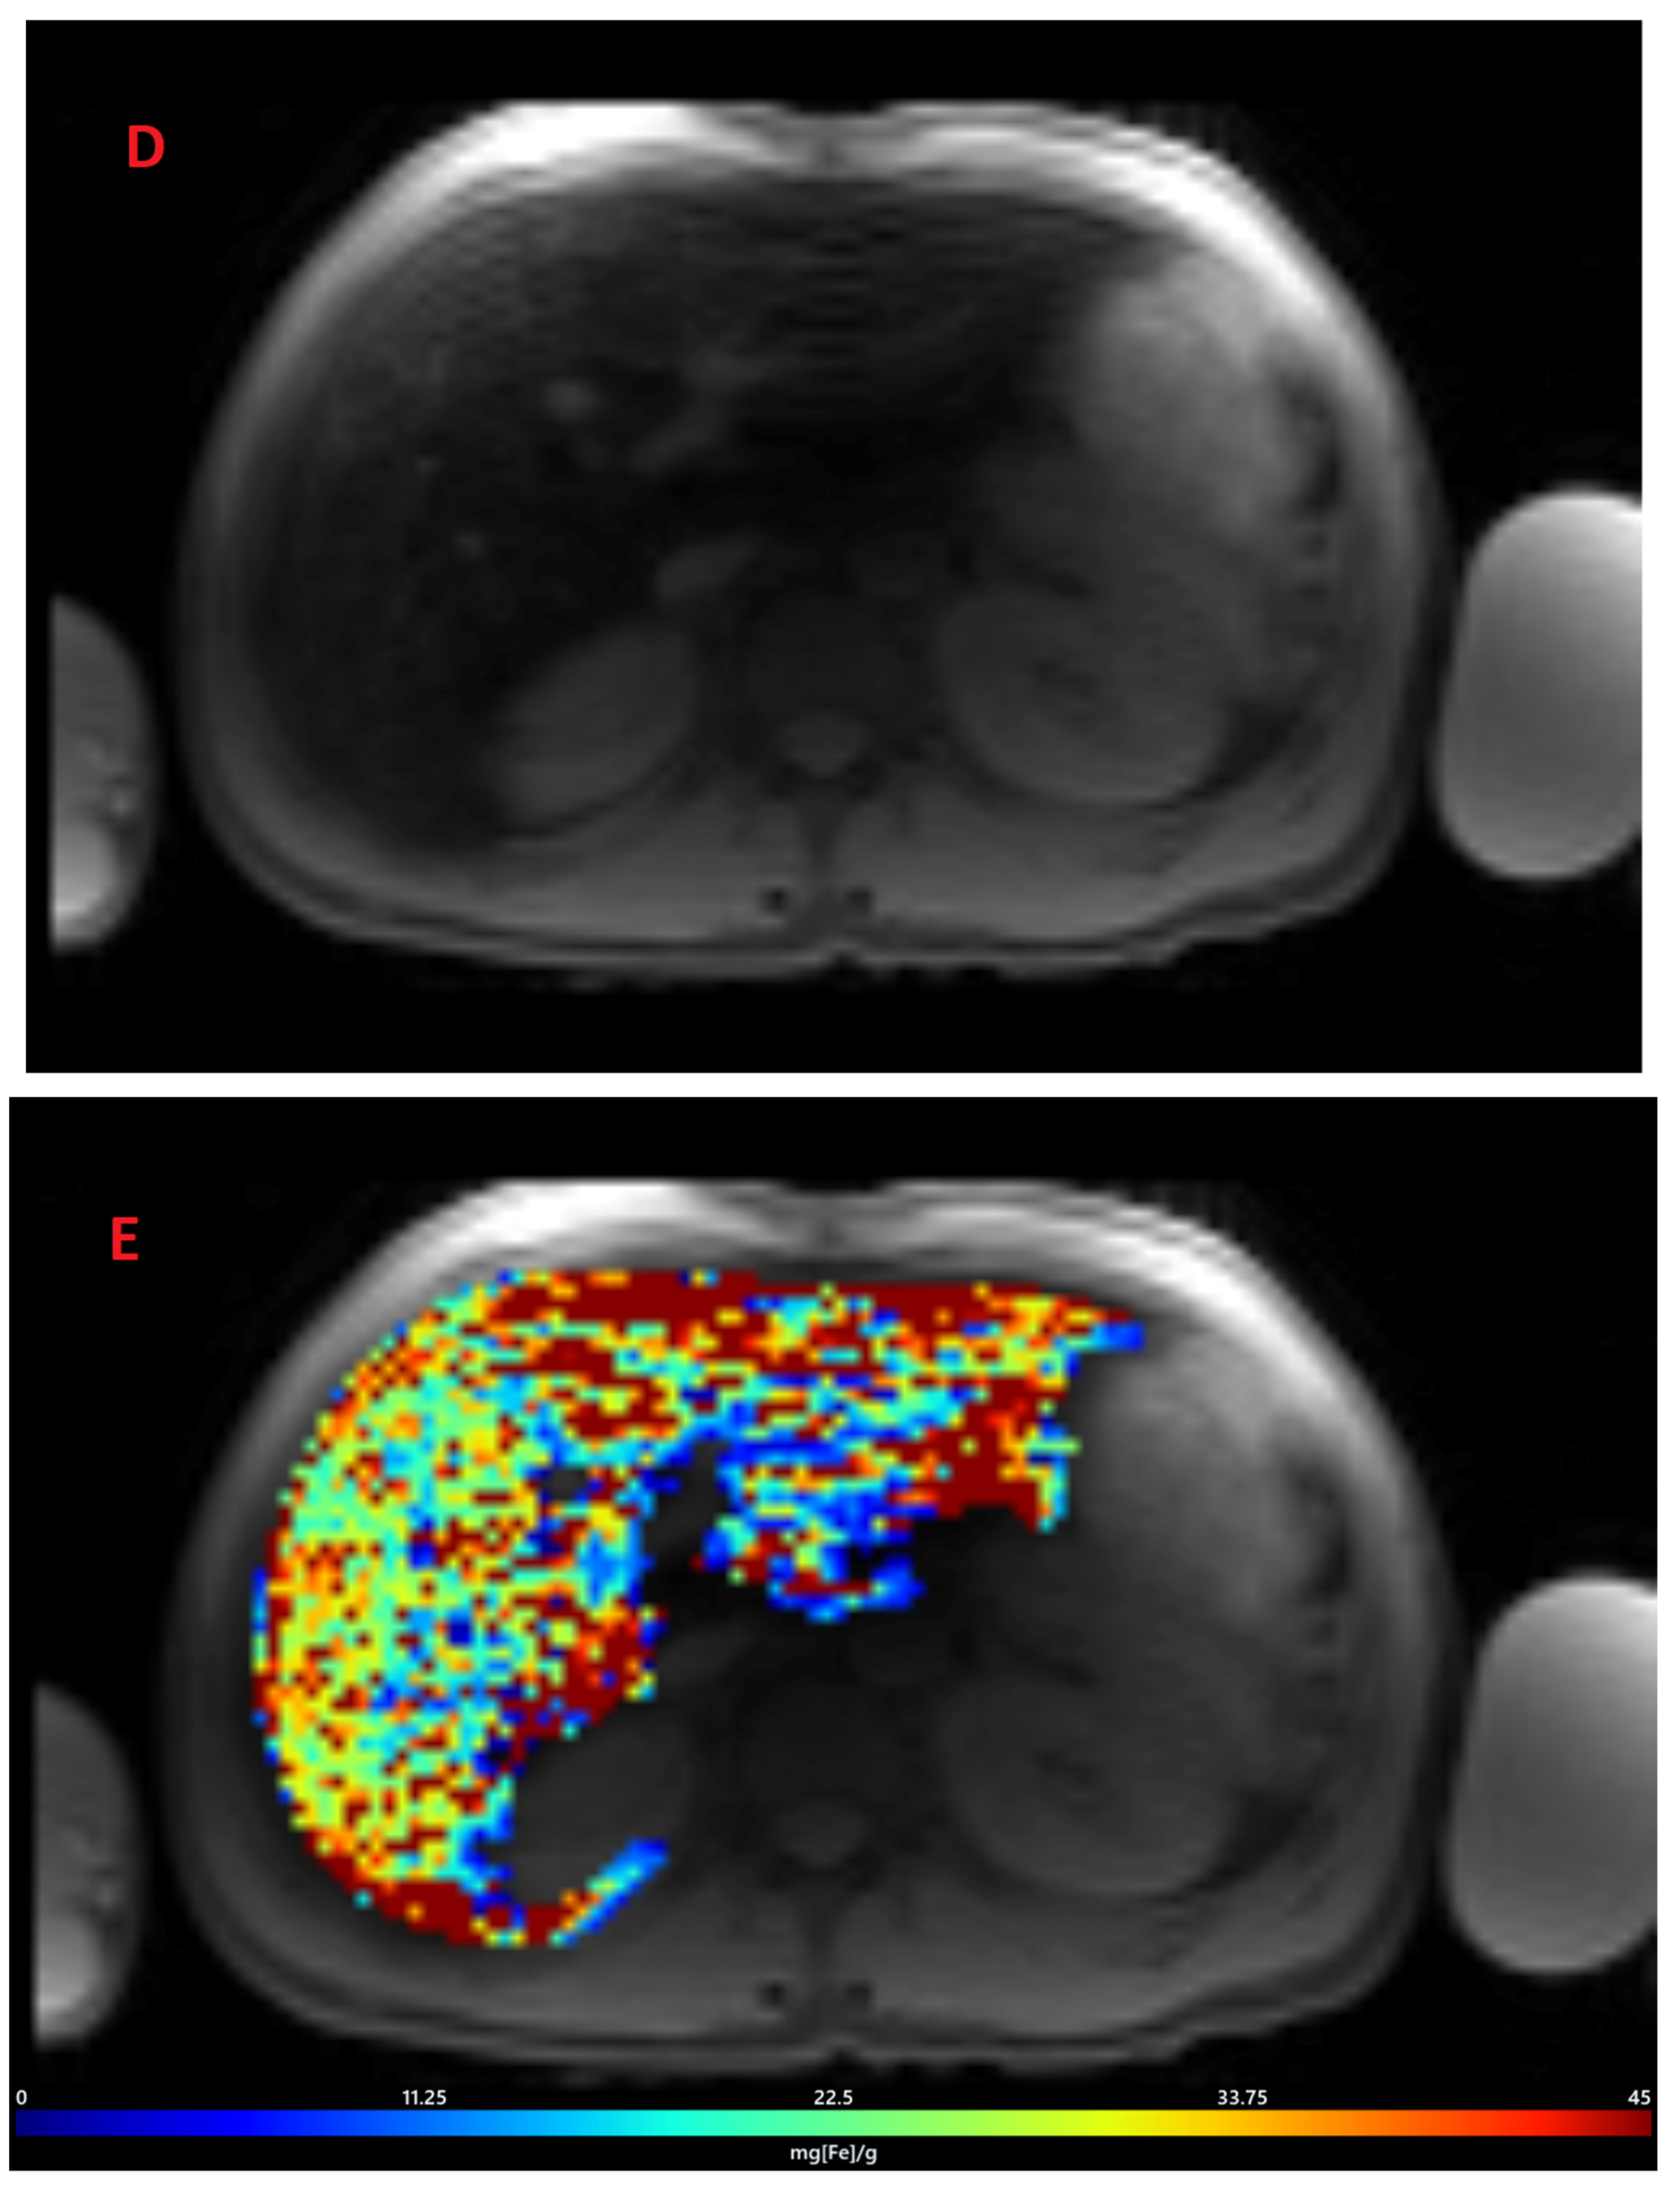

The mean value of LIC R2* at the first scan of the subjects was 10.4 ± 7.9 mg/g (range: 1.35 mg/g to 39.1 mg/g), and the mean value of R2* during the last follow-up was 8.4 ± 6.4 mg/g (range: 0.4 mg/g to 31.1 mg/g). The average rate of change of LIC determined by R2* relaxometry (∆LIC R2*) was −0.0047 ± 0.012 mg/g per month. Representative images in a patient with beta thalassemia assessed for iron overload, which provided an estimated LIC of 26.6 mg/g at time point 1 and an estimated LIC of 31.1 mg/g at time point 2 two years later, are shown in Figure 2. T2* relaxation curves for the two time points are shown in Figure 3.

Figure 2.

Representative images showing (A) the gradient axial echo slices; (B) post-processed liver iron concentration (LIC) map (color scale shows the range of LIC from 0 to 45 mg/g); and (C) R2* map in a patient with beta thalassemia assessed for iron overload at time point 1, which provided an estimated LIC of 26.6 mg/g. The lower panel (D–F) demonstrates gradient axial echo slice, post-processed LIC map, and R2* map, respectively, acquired from a scan performed after two years. The estimated LIC was 31.1 mg/g at time point 2.